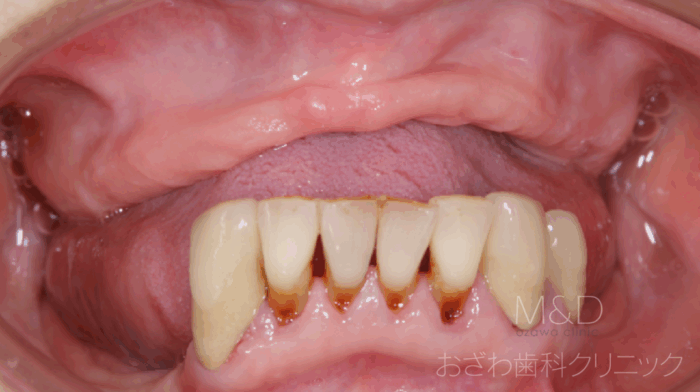

術前

主訴:上の入れ歯が噛みにくい、入れ歯の中に物が入って痛い、

わずらわしい下顎は部分義歯で動くし痛くて、噛めない

上顎の全ての歯が欠損(総義歯)

上顎前歯にはインプラントを埋める骨が全くありません

大学病院で断られた患者さん